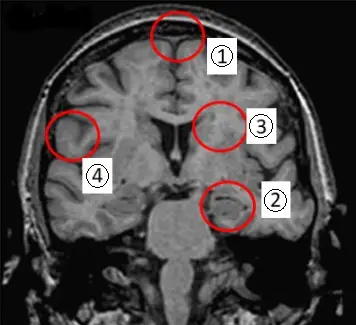

李奶奶是一名失智症患者,主要症狀是忘東忘西,最近更是忘了家人的名字、出門就會迷路。以磁振造影檢查,最主要會發現那一個腦區有萎縮的現象?

本題考查阿茲海默症 (Alzheimer's Disease, AD) 的典型臨床表現及其對應的神經放射影像學 (Neuroradiology) 特徵。

- 臨床表現:李奶奶的症狀為近期記憶力減退(忘東忘西、忘記名字)以及空間定向感喪失(出門迷路)。這是阿茲海默症典型的早期症狀,反映了情節記憶 (Episodic memory) 和空間導航 (Spatial navigation) 功能的受損。

- 病理對應:這些功能主要由大腦的內側顳葉 (Medial Temporal Lobe),特別是海馬迴 (Hippocampus) 及其周邊的嗅內皮質 (Entorhinal cortex) 負責。

- 影像特徵:在磁振造影 (MRI) 上,阿茲海默症患者最早且最顯著的變化是海馬迴萎縮 (Hippocampal atrophy)。

本圖為腦部 MRI 的冠狀切面 (Coronal view) 影像,顯示了大腦的內部結構。讓我們依序辨識標示的解剖位置:

- ① (上方紅圈):指向大腦縱裂 (Longitudinal fissure) 旁的皮質區域,約為扣帶迴 (Cingulate gyrus) 或內側額葉 (Medial fron